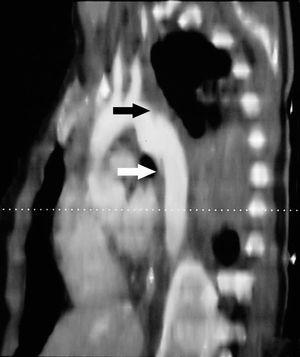

Mujer de 21 años sin antecedentes de interés que presenta politraumatismo tras accidente de tráfico. La paciente es recogida con Glasgow de 15 puntos precisando intubación y conexión a ventilación mecánica por insuficiencia respiratoria. En la tomografía axial computarizada (TAC) torácica de ingreso presenta contusión pulmonar bilateral (*1, fig. 1) y una imagen de "flap" intimal, a 2 cm de la salida de la arteria subclavia izquierda, de morfología irregular y con aumento de calibre compatible con rotura traumática de aorta torácica (*2, fig. 1). En la reconstrucción de la TAC también se aprecia dicha imagen de rotura traumática de aorta (fig. 2). Se procedió de manera urgente a la colocación por vía femoral de prótesis aórtica endovascular con buen resultado final.

Figura 2